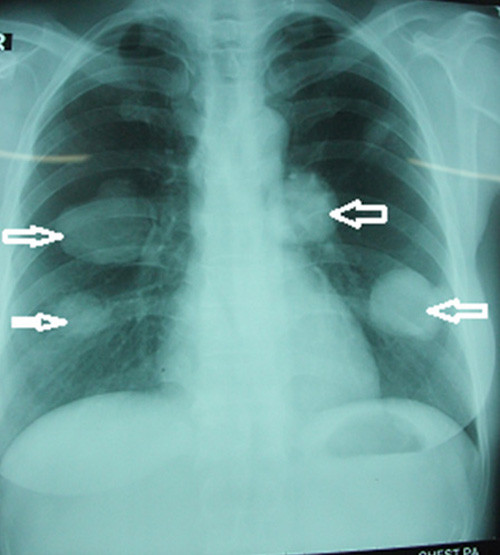

| Kết quả chụp X-quang của chị Cẩm Thị H. có 4 khối u khổng lồ trên phổi, mỗi bên có 2 u. |